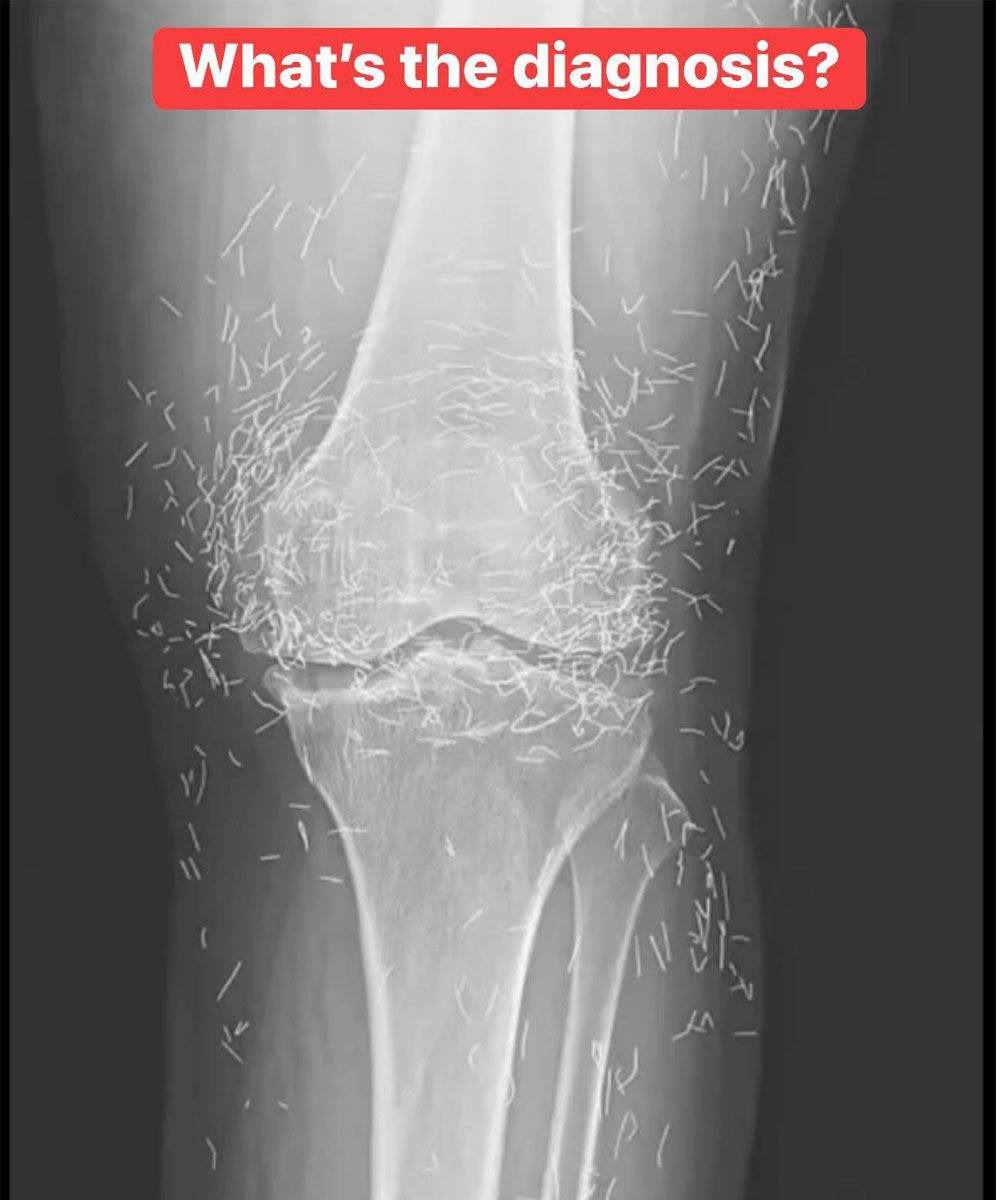

As doctors examined an X-ray image of the knees of an old woman experiencing severe joint pain, they found a gold mine: hundreds of tiny gold acupuncture needles left in her tissue.

In the woman’s acupuncture treatment, the needles, which were presumably made of gold, were intentionally left in her tissue for continued stimulation, the report says.

It could also make it hard for a doctor to read an X-ray. “The needles may obscure some of the anatomy,” Guermazi said.